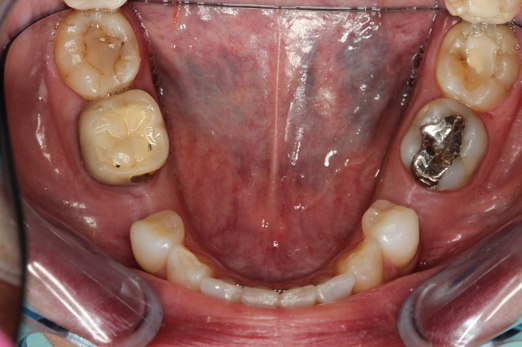

Fig 18. Preoperative image.

Figure 18

Occasionally dentists are presented with extreme challenges with long-term restorations and replacing missing teeth. Dentists must evaluate the patient's condition, develop optimum long-term oral health, and attempt to meet the patient's expectations. Figure 18 showed a class III malocclusion with deep bite, multiple abfractions, and less-than-ideal occlusal plane, but the patient wanted to replace his maxillary right canine only. A discussion with the patient regarding occlusal disharmonies and comprehensive recommendations for full-mouth rehabilitation revealed that the patient had a limited budget for dental care. The patient understood the ramifications of his comprehensive dental needs not being affordable. Decisions were made to atraumatically remove the maxillary right canine (Figure 19) and immediately place a ceramic dental implant (Figure 20). Polytetrafluoroethylene (PTFE) 4-0 sutures were placed to help support soft tissues, and then a full-arch Essix-style retainer with a flowable composite facial veneer was used to provide some esthetics during the patient's healing phase (Figure 21). The implant and the retainer were not to be in contactthe retainer may occlude with the opposing dentition and also be passive in relation to the ceramic implant.